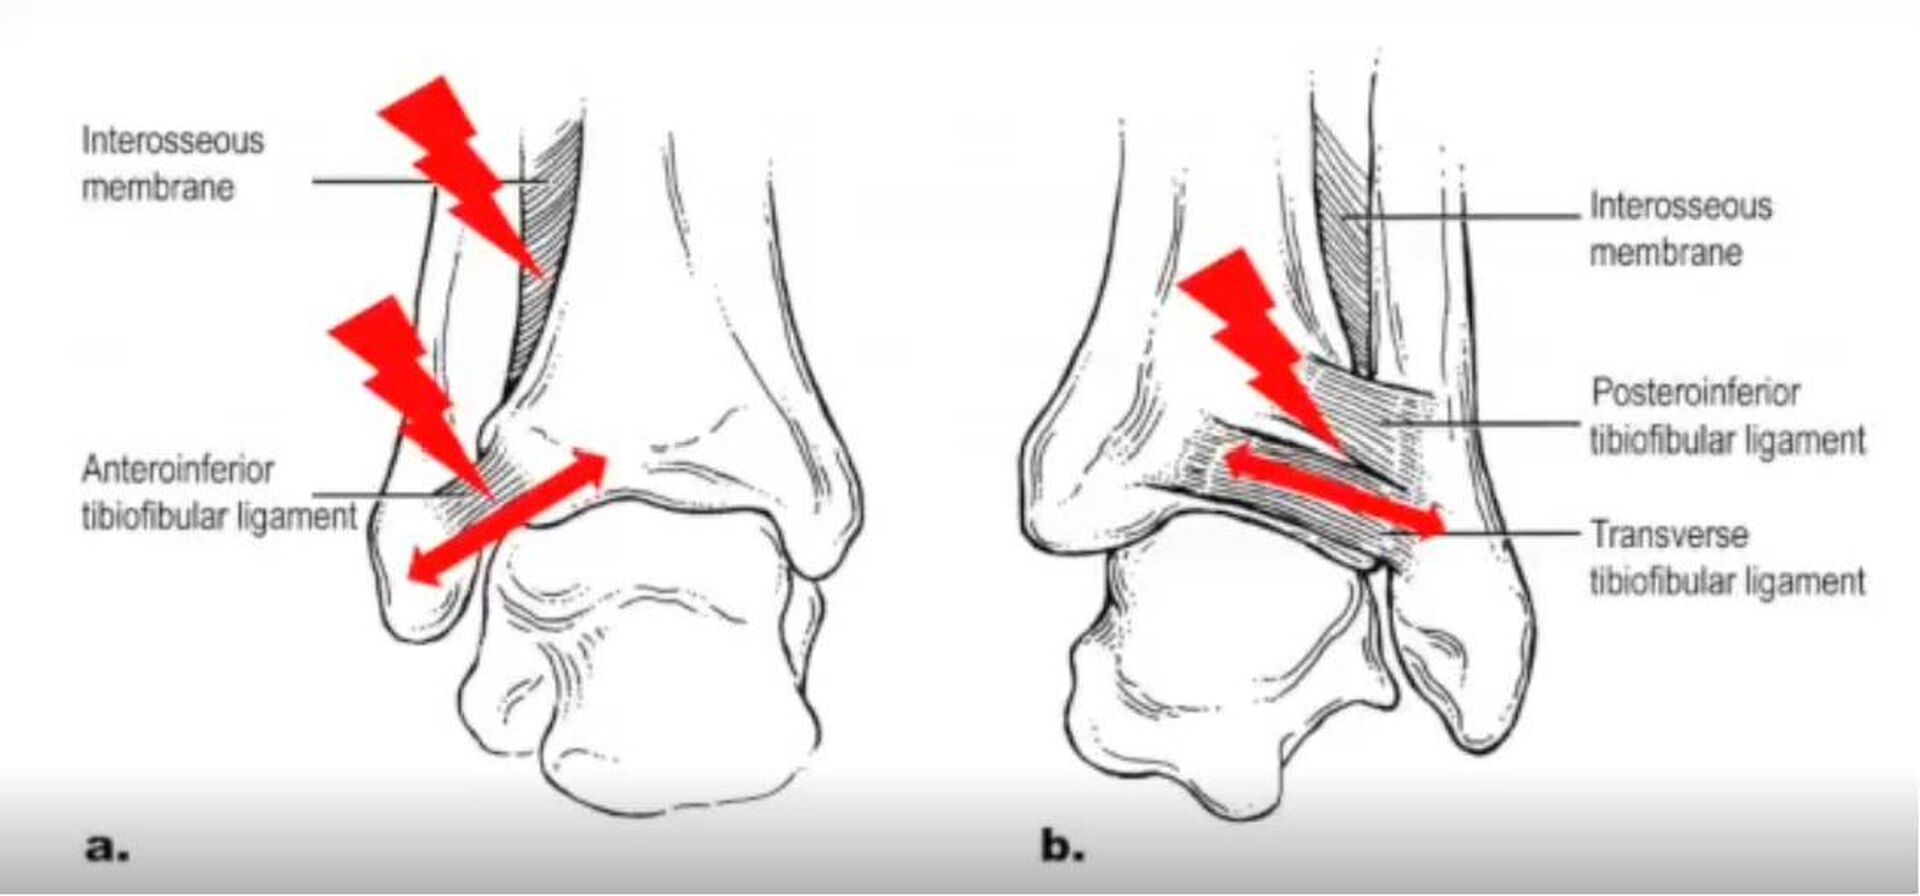

Les traumatismes en rotation sont particulièrement dangereux car la chaussure de ski ne limite pas ce mouvement. Les ligaments entre le tibia et le péroné sont susceptibles d'être rompus, entraînant des douleurs importantes.